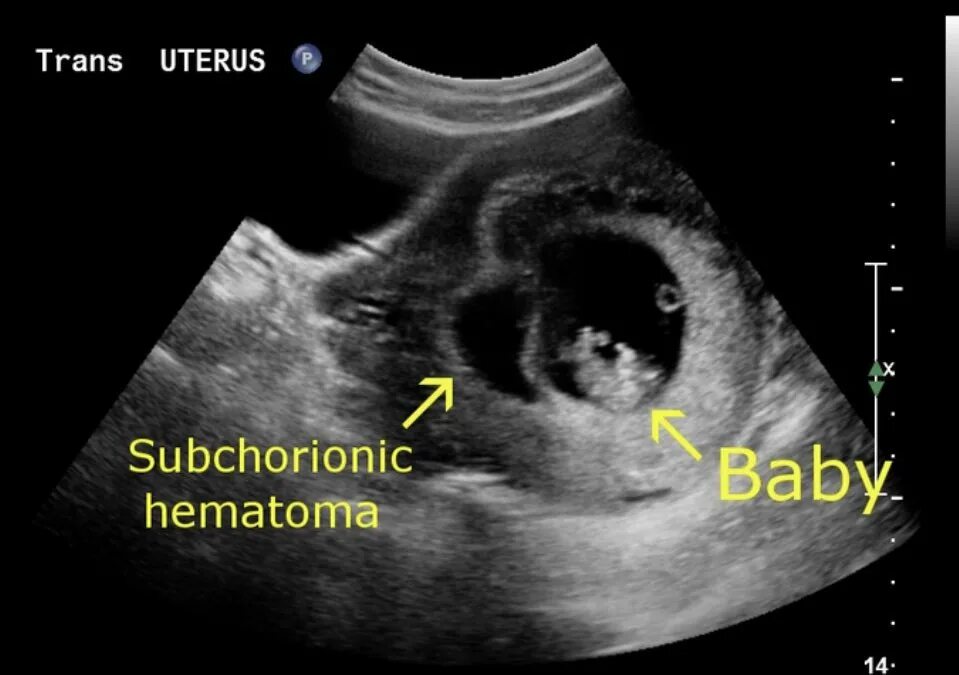

Плацента на 6 неделе беременности